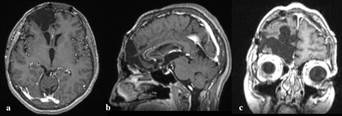

A bifrontal osteoplastic craniotomy was performed, with complete microsurgical excision of a yellow, well-defined, smooth surfaced, and well-vascularized intradural extra-axial mass, infiltrating the dura. There was no immediate correlation between the ipsilateral olfactory nerve and the mass. Surgical time was approx. 4 hours. Multiple tissue samples were acquired from peripheral and central parts of the neoplasm, while the rest was excised employing an Ultra-Sonographic Aspirator. The patient remained in Intensive Care Unit for a 24h gradual reduction of sedation. Post-surgery CT assessment confirmed the total excision. She was discharged two weeks post-surgery with amelioration of symptoms and complete recovery after a month of physical therapy. At that time, she returned to her previous functional and working status with a Modified Rankin Scale of 0 and Karnofsky Perfomance Status of 90 points. Since then she is free of symptoms, with no neurologic or mental function alterations and no recurrence after five years (Figure 2).

The diffuse positivity for CD34 raised concern for solitary grade II dural hemangiopericytoma (solitary fibrous tumor- SFT) and an expert opinion was requested from a specialized center in the USA. In the reference laboratory the initial immunohistochemical profile was confirmed; in addition, the tumor was diffusely positive for SOX10 and negative for STAT6 and MelanA. These findings essentially confirmed the neural crest origin of the tumor and excluded an SFT. The final diagnosis of cellular schwannoma with unusual CD34 diffuse positivity was rendered (Figure 4).

Figure 4 Histopathological investigation: Sections present a cellular spindled to slightly epithelioid cellular proliferation with no significant atypia, low mitotic activity, and foci of necrosis on Hematoxylin and eosin staining (a), arranged in Antoni A (hypercellular) and Antoni B (hypocellular) areas with interspersed Varocay bodies (i). Immunochemical stains show that the neoplasm is diffusely positive for vimentin, S-100(c), SOX10(d), Collagen type IV(e) and CD34(b) while being negative for EMA, desmin, ALK, STAT6, and GFAP with low (<5%) positivity for Ki67 and less than 3/10 HPF nuclear movements. A scale is provided to present the magnification.